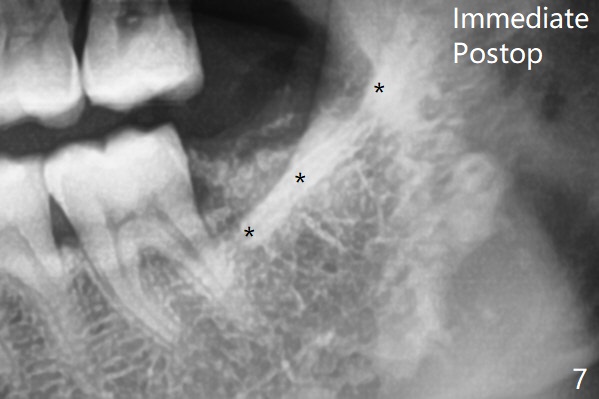

Since no buccal trough is made for extraction, the external oblique ridge (*) is present at #17 and 32 before and after surgery. Bond Apatite is placed with Collagen Plug (Fig.7).